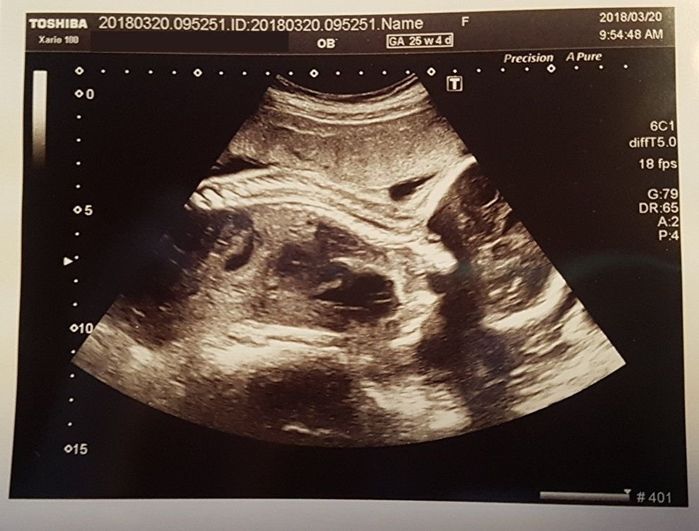

妊娠25週目 がっちりとした骨、胎動もポコポコ

上に背骨、右に頭の骨が見えています。頭の骨の中に、脳ができてきているのだと思うと感慨深いものがあります。このころは体がカメラに向いていないことが多くて、顔が見られないのが残念。

血液検査による不規則抗体の結果は陰性でしたが、これからも継続して検査が必要とのこと。私が不安になる一方で、おなかを蹴ったり押したりする元気なわが子。「大丈夫」と勇気づけられました。